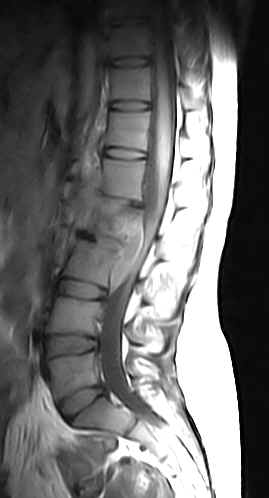

The L1, L2 and L3 vertebral bodies show hypointense areas on the T1W images and these turn hyperintense on the T2W images. The L1-L2 and L2-L3 intervertebral discs are also involved. There is an anterior epidural lesion at the L2 and L3 vertebral levels. It is hypointense with a hyperintense rim on the T1W images and hyperintense with a hypointense rim on the T2W images. This would be suggestive of an abscess. Slight prevertebral soft tissue extension is noted. The psoas muscles are bulky bilaterally and show presence of abscesses. A similar lesion is noted within the left paraspinal muscles.

·                     There is replacement of the normal marrow by inflammatory tissue (with hyperemia, edema and pus) and this is usually hypointense on the T1W images and turns hyperintense on the T2W images. It may be found in the subchondral region or may be seen as a more diffuse involvement. The sagittal images may show it to be a disc centered process. Contrast enhancement is useful in those who have an inhomogeneous marrow pattern and is of marginal value in those with fatty vertebral marrow. Fat saturation techniques help. Typically the hyperemic and osteomyelitic bone enhances. Skip lesions  may be seen with multivertebral involvement and relative sparing of the intervertebral discs. Involvement of the posterior elements is fairly common.

·                     Tuberculosis tends to involve the soft tissues commonly with abscess formation. Large paravertebral or psoas abscesses (calcifications may be seen) are commonly involved. These may be out of proportion to the degree of involvement of the vertebra or disc. Abscesses may also be seen in the paraspinal region and epidural space. The abscesses are usually located ventrally in the cervical and lumbar spine and posteriorly in the dorsal spine. The leptomeninges may be involved. Intraosseus abscesses may be seen. The abscesses are invariably seen to have a centre which is isointense to hypointense to normal muscle with a slightly hyperintense rim on the T1W images. On the T2W images the centre is hyperintense and the rim hypointense. Contrast enhancement of the rim is noted. These lesions usually yield drainable pus. It may be difficult to distinguish phlegmon (inflammatory mass of granulation tissue) from an abscess. Phlegmon usually shows diffuse contrast enhancement. This inflammatory tissue may tunnel beneath the paraspinous ligaments.